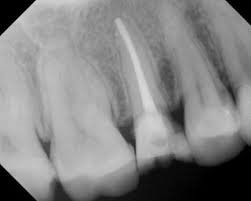

Zdjęcie punktowe – prześwietlenie kilku zębów w wysokiej rozdzielczości /zapis w formie cyfrowej /

Leczenie kanałowe zęba jednokorzeniowego – opracowanie chemiczno -mechaniczne kanału korzeniowego , pomiar długości oraz wypełnienie kanału korzeniowego odpowiednim materiałem w zębie jednokorzeniowym.

kanal zęba

Wypełniony kanał zęba jednokorzeniowego.